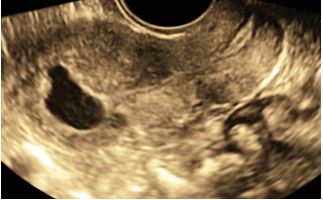

Immagini in 3d di adenocarcinoma endometriale in cui si denota un’infiltrazione del miometrio superiore al 50% dello spessore miometriale e assenza di coinvolgimento dello stroma del canale cervicale.